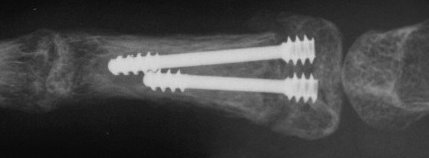

| Proximal phalanx fractures are a common problem with many treatment options. These images illustrate a technique of stabilization using intramedullary Herbert screws placed percutaneously through the base of the proximal phalanx. Provisional fixation is obtained with K wires which are replaced with Herbert screws, which simply follow the soft tissue path of the pin tract to the bone. Self tapping screws are not used in this technique, as the cutting threads catch on soft tissues. |

| A second case, five weeks after injury with early callus, treated with similar technique after percutaneous fracture mobilization with a small elevator. |